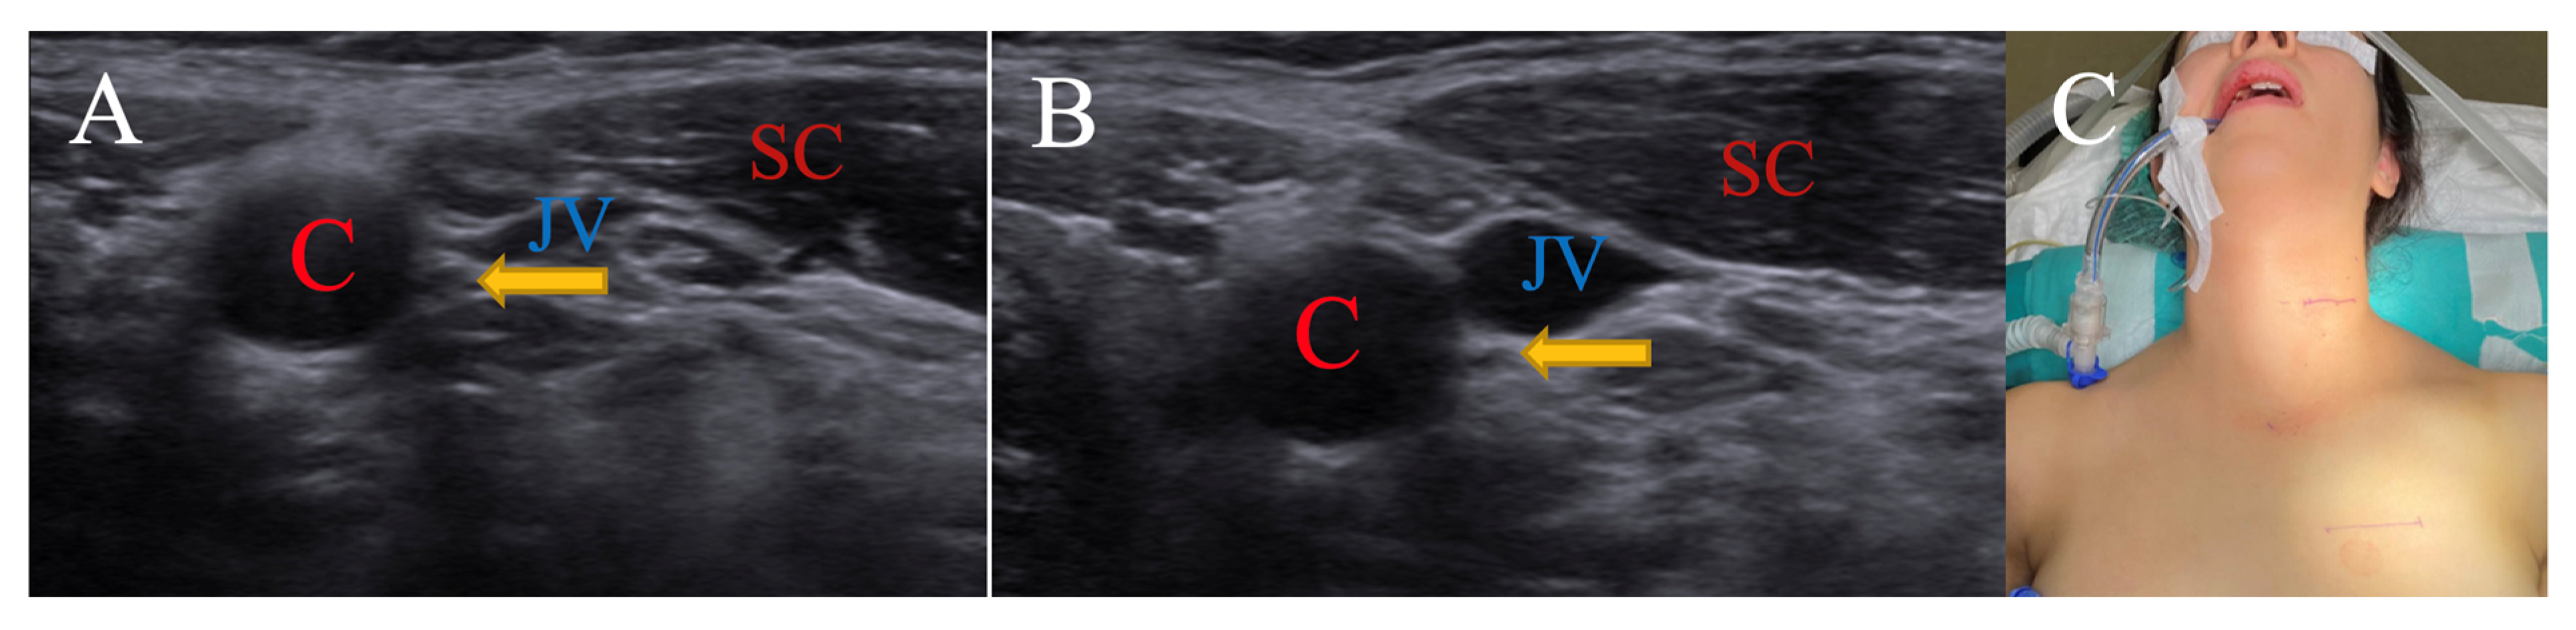

3.1.2. Neutral Position for Sternocleidomastoid Muscle

| SCM | Sternocleidomastoid |

| C | Carotid artery |

| JV | Jugular vein |